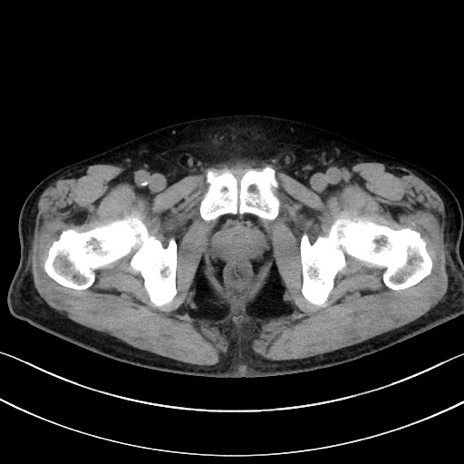

症例15(横断像)

【症例】70歳代男性

【主訴】腹痛

【現病歴】今朝から腹痛あり。全体的に痛い。特に左上の方。排ガスが今日はない。冷や汗が出る。

【既往歴】直腸癌術後

【身体所見】左側腹部〜上腹部に圧痛あり。腹膜刺激症状明らかなではない。軽度反跳痛。左下腹部に術後瘢痕あり。

【データ】WBC 7700、CRP 0.02